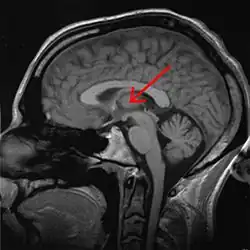

Thalamus marked (MRI cross-section)